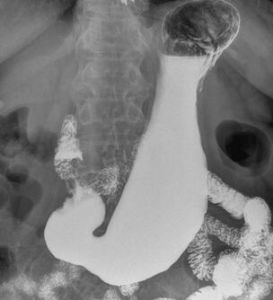

1.鋇餐檢查

可見十二指腸瘀滯及擴張徵象,或在十二指腸某處鋇劑突然受阻,有時可見逆蠕動。

2.X線鋇餐檢查特徵:十二指腸水平部見鋇柱中斷(突然垂直切斷);受阻近段腸管強有力的順向蠕動及逆蠕動構成的鐘擺運動;俯臥位時鋇劑順利通過,逆蠕動消失。